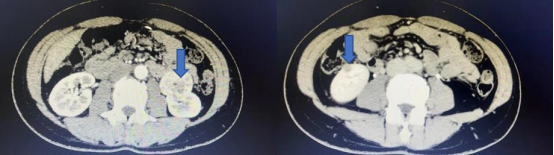

今年48岁的齐女士因体检发现左肾长了一个4公分大小的肿瘤,住院后为进一步明确诊断,完善肾脏增强CT,结果意外发现右肾也存在一个大小约1公分的肿瘤,王女士得知后决定完善全身PET-CT检查,PET-CT提示双肾病变,未见转移。王春阳告诉患者家属目前患者双肾肿瘤还没有转移,尽快手术是最好的治疗方案。为完整切除双侧肾肿瘤,并且最大限度保留肾脏功能,同时实现微创效果,在患者及家属积极要求下,王春阳团队决定为患者行机器人辅助腹腔镜下双肾肿瘤切除术。

王春阳介绍,双肾肿瘤一期同时切除手术难度较大,但同时机器人辅助腹腔镜手术系统对于双肾肿瘤一期切除有其独有的优势——切口仅仅增加一个即可完成双肾肿瘤的完整切除,并且可以最大限度地实现“零缺血”,即术中可不阻断肾动脉而完整切除肿瘤,最大限度的保留了肾脏功能,为患者之后的生活质量提供了保证。